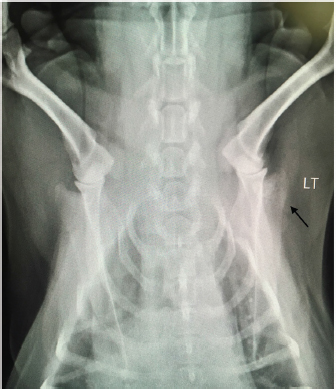

An 8-year old female spayed beagle presented with a complaint of intermittent left front limb lameness of 4-day duration. Obvious lameness was not appreciated on physical examination; however, considerable pain was apparent upon palpation of the humeroscapular joint. The remainder of the physical examination was normal with the exception of dental calculus and a body condition score of 7/9. Radiographic study under sedation was recommended, but the client opted for symptomatic treatment of pain and bed rest. Tramadol was prescribed at 4.6 mg/kg every 12 hours for 14 days. The patient returned 8 days later for persistent lameness. Per the client, Tramadol was given at the recommended dosage for three consecutive days, but was discontinued due to lack of improvement. Pain was again elicited on palpation of the left humeroscapular joint, as well as with its extension and flexion. Radiographs with consult were approved at this visit, which revealed multiple small regions of radiolucency in the distal aspect of the spine of the left scapula, including the acromion process (Fig. 1). Radiographic consult by a board-certified radiologist stated a concern for an aggressive lytic lesion; possibly representing a neoplastic process such as a primary mesenchymal tumor or a round cell tumor. The radiolucencies were subtle, so the possibility that it represented a superimposition artifact could not be ruled out. The radiologist recommended an ultrasound evaluation of the affected scapula. If a cortical irregularity were to be identified on ultrasound, bones aspirates should be obtained for cytologic evaluation. Alternatively, follow-up radiographs were suggested to be evaluated in 3–5 week to reassess the appearance of the left scapula. Carprofen was prescribed at 2.2 mg/kg twice daily for 7 days to evaluate the patient’s response while awaiting the client’s decision. The client called 2 weeks after the last appointment stating she had taken the patient to a different veterinary clinic where a second set of radiographs were taken, which revealed a more pronounced radiolucency in the left scapula (images not available due to analog radiographs being taken at a different clinic).

Fig. 1. Radiograph showing multiple small regions of radiolucency in the distal aspect of the spine of the left scapula, including the acromion process (arrow). LT=left.